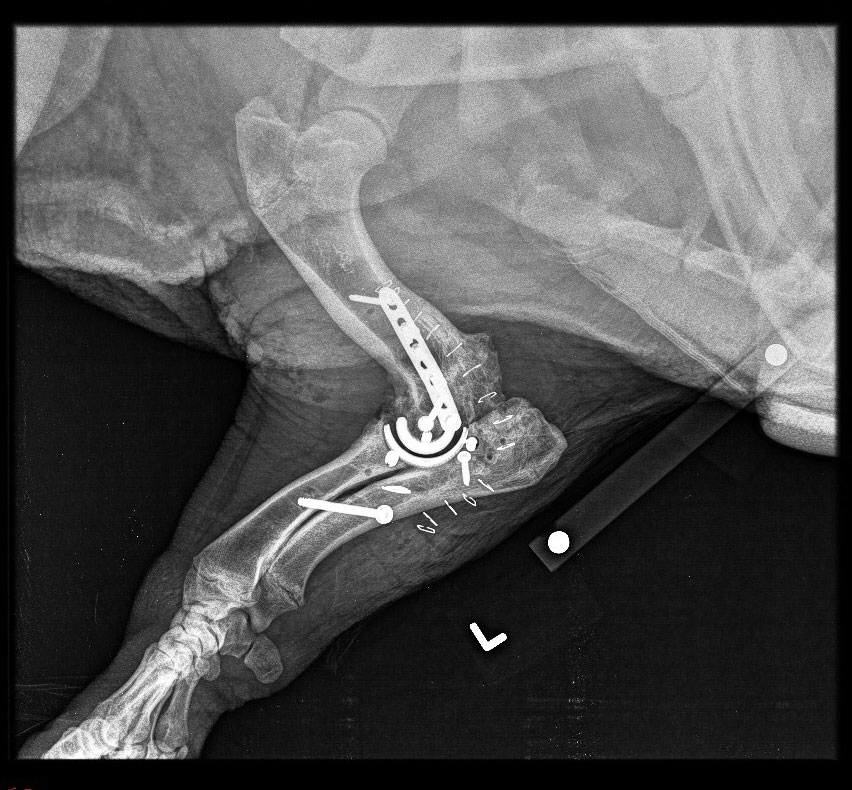

Different from canine joint replacements, the pig’s bulkier musculature required the team to approach the elbow from an outside rather than an inside angle. The surgeons then used specially 3D-printed instruments to accurately place the prosthetic and confirmed its correct location with post-operative x-rays. “Willow's elbow replacement went very well as a result of outstanding planning and effort by numerous clinicians, staff and students,” McOnie said.